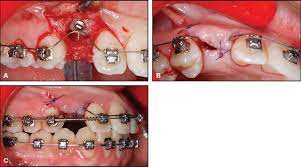

Open Eruption Technique - Management Of Maxillary Canine Impaction / Despite the unconcealed allocation, the outcome duration of canine's eruption is probably in low risk of bias as the protocol of open and closed technique is mentioned clearly, any possible confounders (age, depth of impaction) have similar distribution at baseline among groups and the definition of eruption is objective.. Dr vanarsdall recommends open exposure with a repositioned gingival flap (pediculated connective tissue graft) above the impacted canine. Despite the unconcealed allocation, the outcome duration of canine's eruption is probably in low risk of bias as the protocol of open and closed technique is mentioned clearly, any possible confounders (age, depth of impaction) have similar distribution at baseline among groups and the definition of eruption is objective. The mean surgical time for open eruption technique was lesser when compared with closed eruption technique (p = 0.000). An attachment may be placed during or after the procedure. Patients perception of recovery after exposure of impacted teeth:

The open eruption technique may be performed in two different ways, as described below.

Window technique this represents the simplest form of open exposure. The open exposure technique consists of surgical removal of the tissue covering the tooth, leaving it exposed to the oral cavity. 26,27 in the case shown here, closed eruption was chosen for the impacted central and. Within the different approaches there exist two main options for the subsequent eruption of the impacted teeth (6): Open eruption technique the open eruption technique was the first method used to uncover impacted teeth.

Chaushu s(1), becker a, zeltser r, vasker n, chaushu g. Preorthodontic exposure and autonomous eruption The open exposure technique consists of surgical removal of the tissue covering the tooth, leaving it exposed to the oral cavity. Given the reported success of forced eruption, the technique requires… continue reading The present study provides information to patients and clinicians. Duration of surgical procedure (in min) click here to view Dr vanarsdall recommends open exposure with a repositioned gingival flap (pediculated connective tissue graft) above the impacted canine. Apically position flap the goal is to choose a technique that exposes the canine within the a zone of keratinized mucosa without involvement of the cementoenamel junction 27. The open eruption technique may be performed in two different ways, as described below. If the canine crown is positioned distal to the mesial aspect of the lateral incisor, an open technique is performed. Forced eruption can preserve the natural root system and related periodontal architecture, resulting in years of additional service for the patient. Open eruption through a window; In this technique sufficient space.